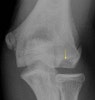

1. Capitellum fragmentation usually seen on X-ray

X-ray : 소두의 골연골염(Panner’s disease)